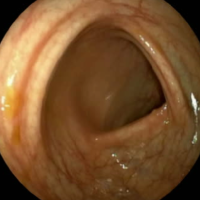

O esôfago é uma estrutura muito importante no suporte alimentar das pessoas. Apresenta processos motores pela sua musculatura de enviar os alimentos para o estômago e estrutura valvulares para abrir e fechar permitindo a sincronia na alimentação. Como tem uma estrutura superficial (a mucosa) pode albergar doenças e a que mais se apresenta ,são representadas pelo refluxo do conteúdo gástrico para o mesmo. Também a sua musculatura e valvular podem apresentar disfunções.